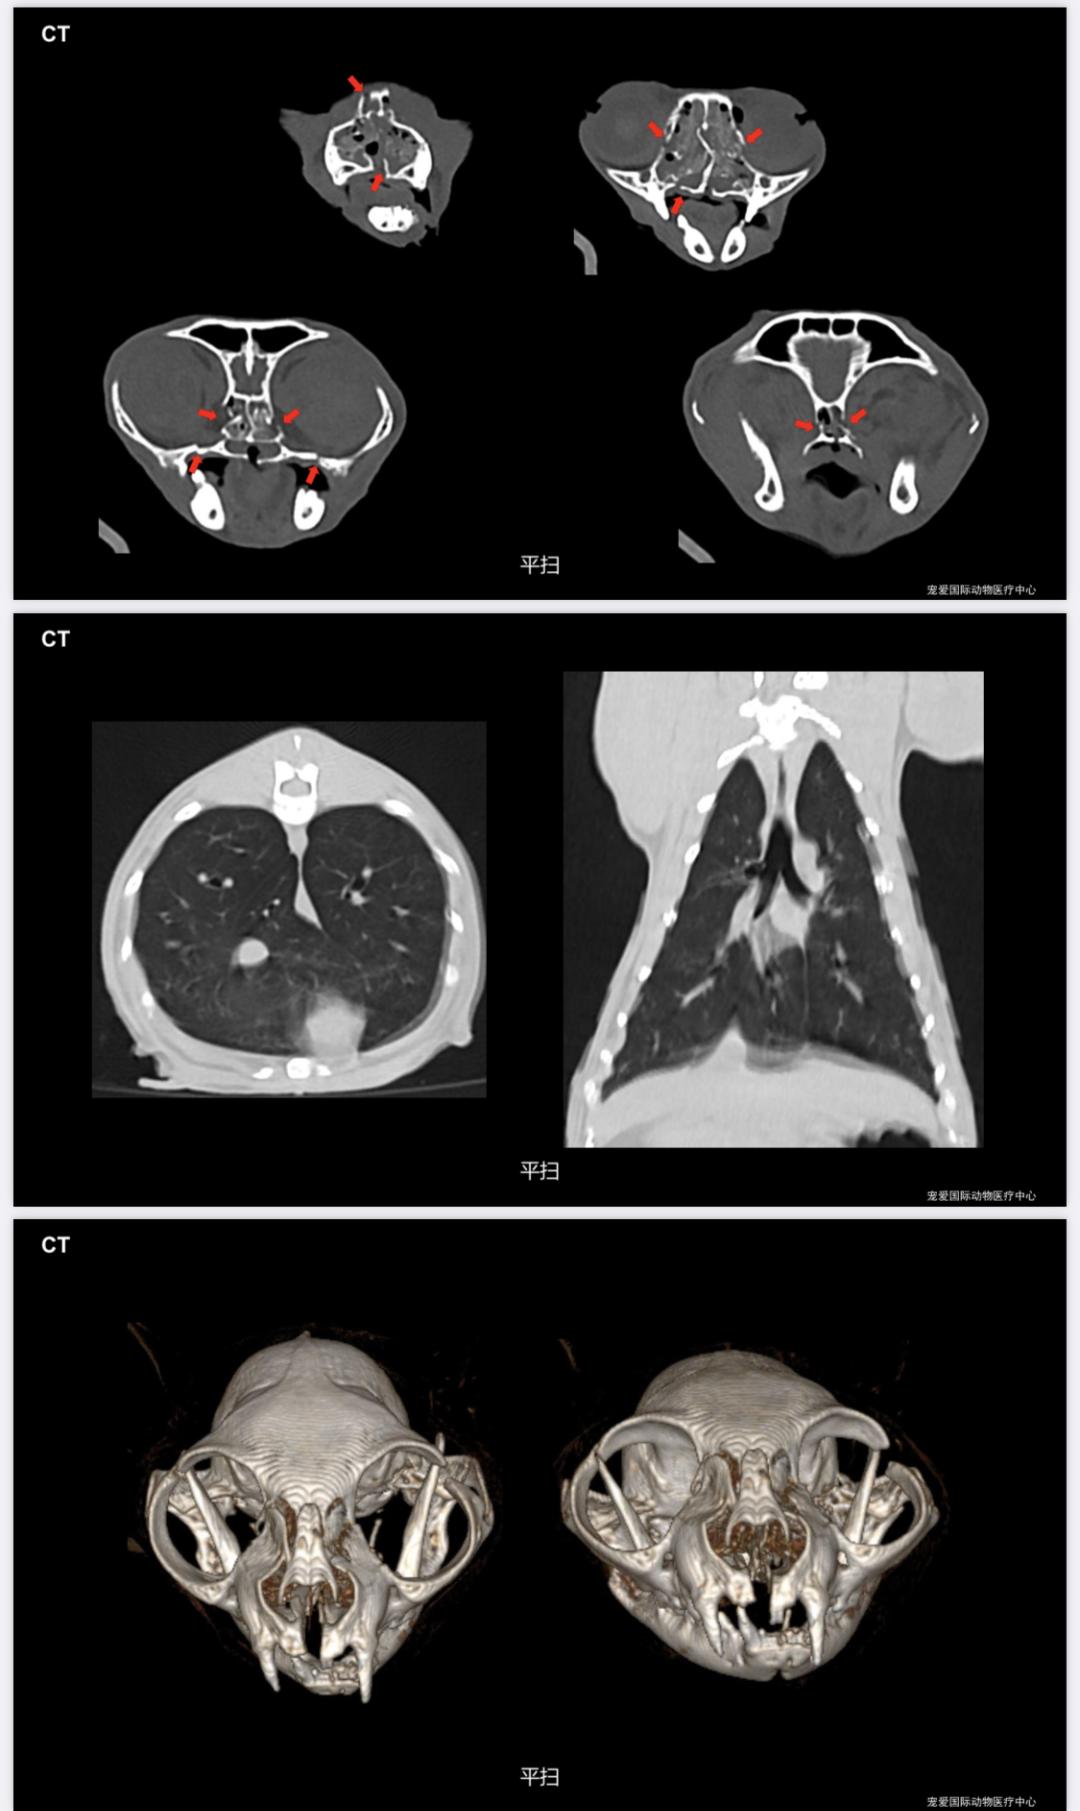

胸腰椎、四肢未见明显骨折;面部、鼻腔、多处骨折。

面部多处骨折、腭裂、贫血

4.转诊中心医院CT 检查

法斗呼吸不畅、运动不耐受,通过CT扫查发现鼻咽部息肉、软颚肥厚↓↓